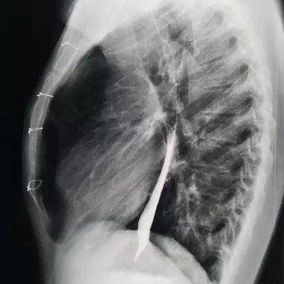

The chest wall exhibits a large area of prominent and bilaterally symmetrical protrusion, predominantly in the upper half. There are also mild depressions on both sides of the lower half of the chest wall.

First, two 3 cm incisions were made on each side of the chest wall, followed by a 2 cm incision along the old surgical scar in the middle of the chest wall. Two bars were then placed on the protruding bone structures of the chest wall to perform the Wenlin procedure. Since the anterior chest wall is a rigid whole, correcting and pressing down the protrusion in the upper chest often causes a secondary depression below it. To address this, a third bar was inserted into the chest cavity to perform the Wung procedure, thereby elevating the depressed areas. Ultimately, the patient’s chest wall deformity was corrected, and the surgery achieved a satisfactory outcome.